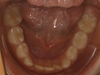

Manque de place pour l'évolution des incisives définitives inférieures

Le manque de place à l’arcade inférieure peut empêcher les dents définitives d’évoluer normalement. Ceci peut se traduire par deux situations cliniques :

• un encombrement antérieur important (« chevauchement » ou évolution des incisives latérales en arrière des incisives centrales) ;

• la perte prématurée de dents de lait. Sur la photo, trois incisives définitives ont fait tomber quatre incisives temporaires. Il peut arriver que quatre incisives définitives fassent tomber les quatre incisives de lait, et une ou deux canines de lait. Dans ce cas, les dents paraissent alignées mais il existe malgré tout un manque de place important.

Pourquoi traiter ?

Un traitement précoce permet aux dents définitives d’évoluer normalement, et peut permettre d’éviter les traitements avec extraction de dents définitives à l’adolescence.